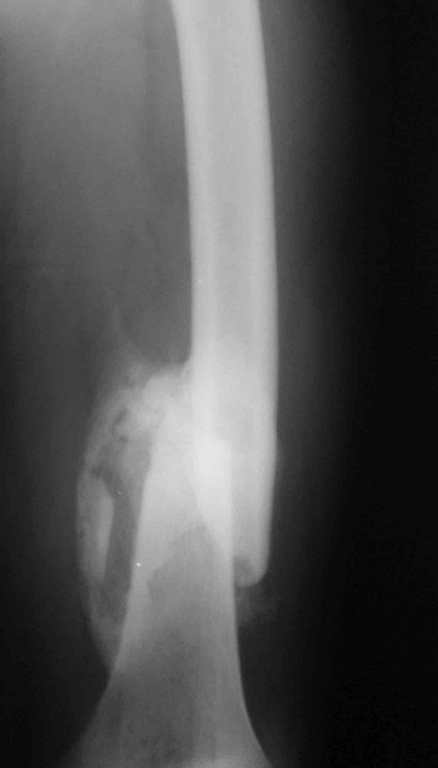

[Ortho] 32- летний пациент с переломами обоих бедер после неудачного оперативного и консервативного лечения.

Имя     : femR 2.jpg